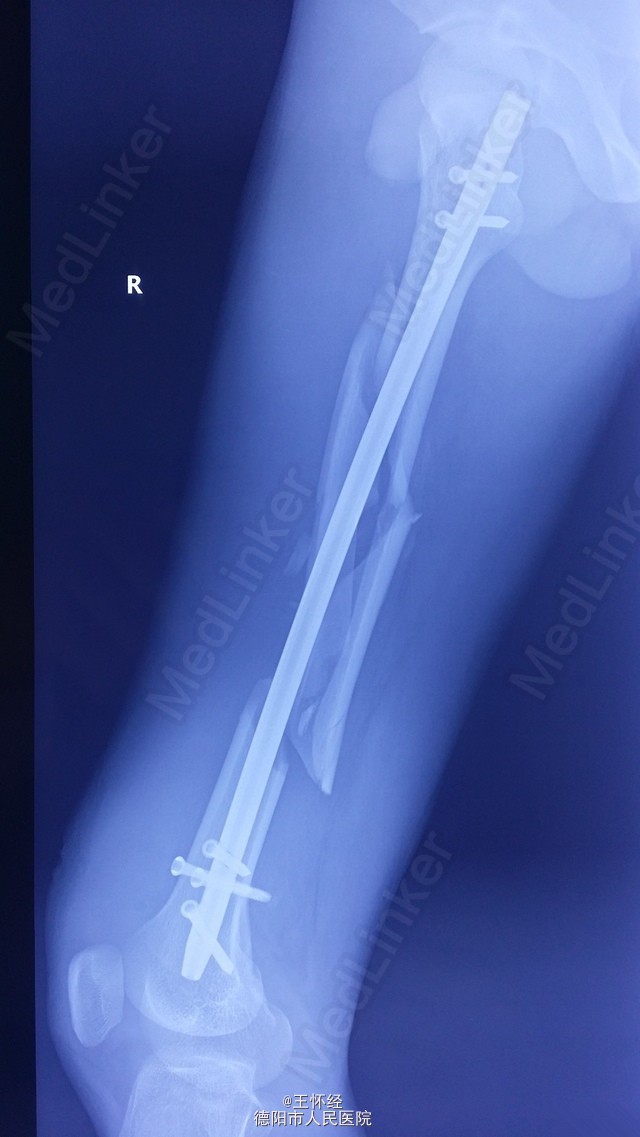

右股骨干粉碎性骨折一例

患者男性,26岁,重物砸伤右大腿后畸形1天,外院转入;予闭合复位髓内钉固定,由于为长节段骨折,骨折距离股骨髁较近,固定不够稳定,术后有骨不连、内固定失效的风险,故加上阻挡钉可以增加骨折固定的稳定性。